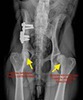

ROTURA LIGAMENTO CRUZADO ANTERIOR

¿POR QUÉ ES IMPORTANTE EL LIGAMENTO CRUZADO ANTERIOR ( LCA)? La rodilla consta de 4 ligamentos que “sujetan” los dos huesos de la articulación: fémur y tibia. De todos ellos, el más importante para el funcionamiento de la rodilla es el LCA. Si éste sufre una rotura, ya sea total o parcial, la estabilidad se ve comprometida y por una serie de fuerzas musculares (la fuerza resultante se llama “empuje tibial”) la tibia se desliza y arrastra sobre el fémur . Las causas de esta rotura pueden ser